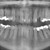

Задава се краят на четката за зъби, след като учени откриха лекарство, което след поставяне върху загниващ зъб, спира процеса и напълно го възстановява, пише в. "Метро", цитиран от БТА.

Вместо пациентите да се подлагат на поредната пломба, зъболекарят в близко бъдеще ще може да напои късче гъба с лекарството Tideglusib и да я постави в отворения зъб.

Препаратът спира гниенето и след време зъбът започва сам да се изгражда наново. Това означава, че в скоро време и четката за зъби и пломбите ще останат в миналото. Последните отслабват структурата на зъба, предизвикват инфекции и водят до по-широки кухини. Разработката е дело на проф. Пол Шарп от лондонския "Кингс колидж".

По неговите думи при пломбите се заменя жива тъкан с инертен цимент. С препарата Tideglusib се стимулират стволовите клетки в центъра на зъба. Те впоследствие се развиват в специализирани зъбни клетки, наречени одонтобласти.

В процеса се получава увеличено производство на дентин, който поправя по естествен начин възникналите дефекти в зъбната структура. Лекарството не е непознато за медиците. То широко се използва като потенциално лечение за Алцхаймер.